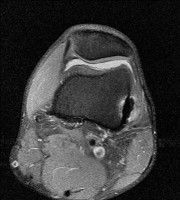

무릎 mri 간단히 봐주실 수 있으시나요 ㅠㅠ

안녕하세요 8년전 십자인대 수술하고 최근 무리한 운동에 무릎 불편감이 생겨서

mri 찍었습니다.

진단결과는 첫 찍은 병원에서 활액막염 이라는 진단을 받았습니다. 혹시 봐주실 수 있으실까요?

• 안녕하세요. 강성주 의사입니다.

올라온 MRI가 단편적이라서 정확한 진단에 어려움이 있지만 십자인대에는 큰 이상이 있지는 않은것 같으며, 무릎관절내 물이 있는 것으로 보아 활액막염의 진단이 맞을 것 같습니다.

하지만 단편적인 영상이기 때문에 촬영병원에서 정확한 판독지 등을 받으시는 것이 좋겠습니다.